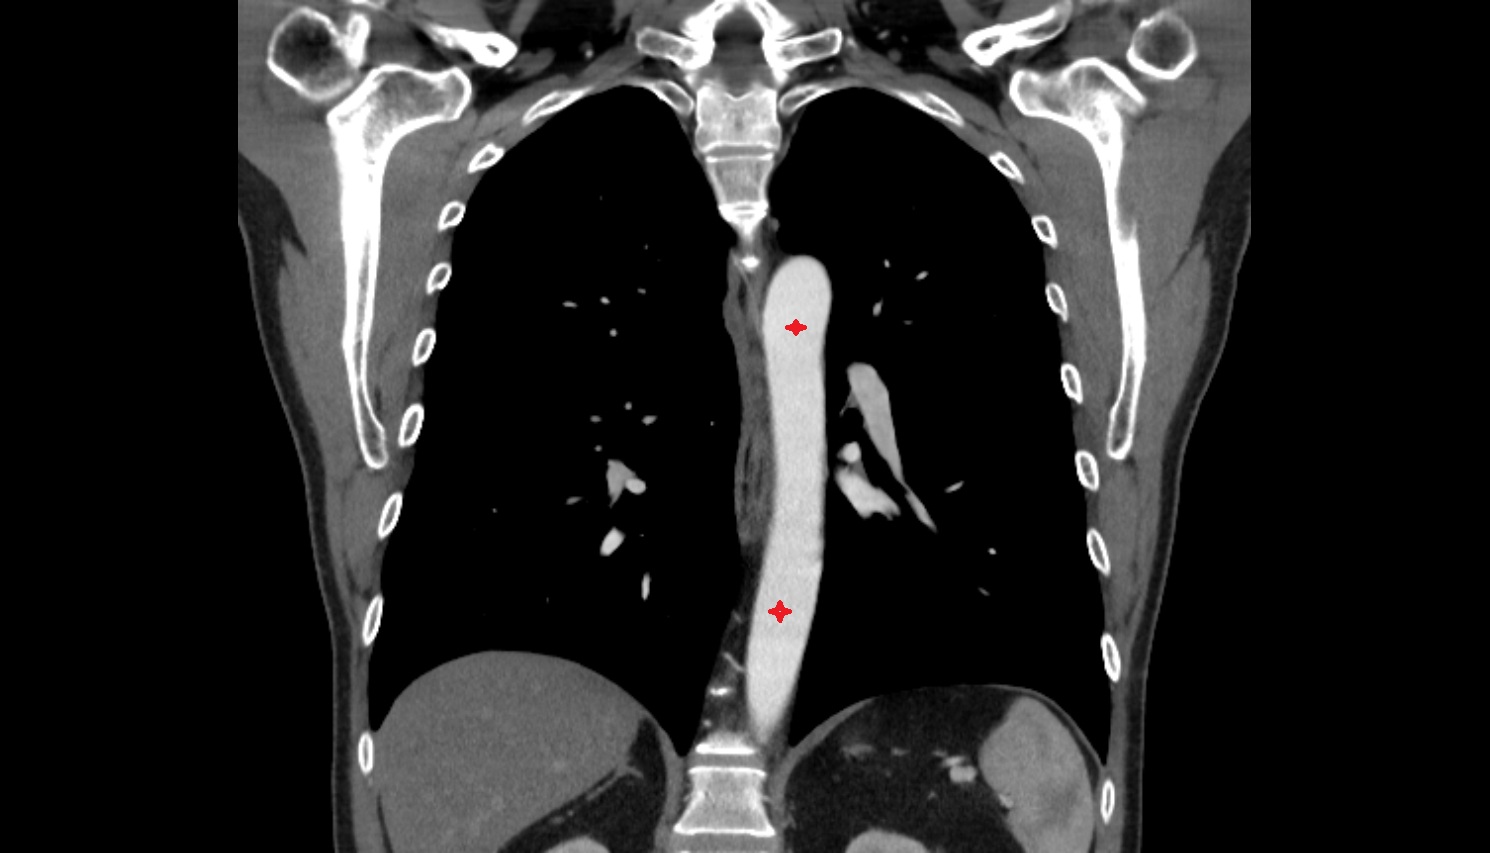

- Thoracic part of esophagus

- Descending thoracic aorta

- Esophagus